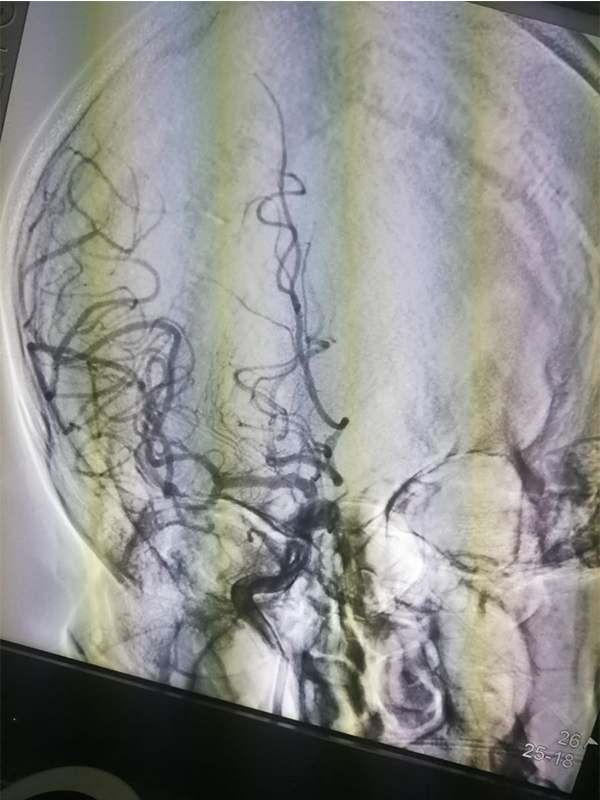

Solitaire 6mm 20mm ( 4 5)